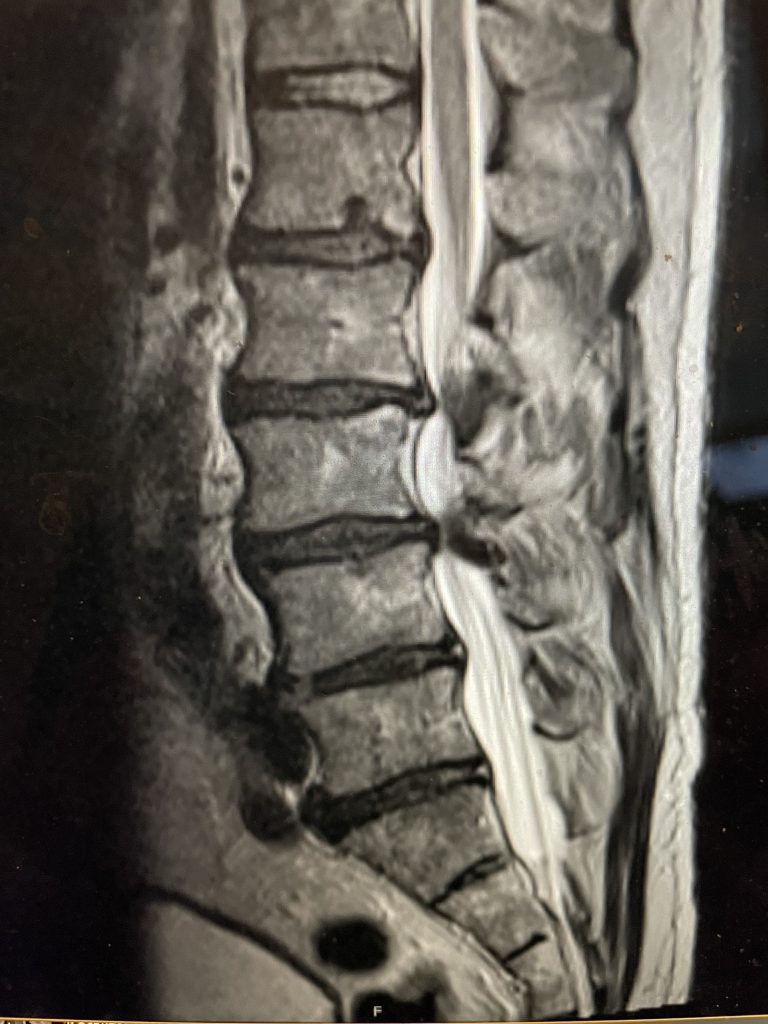

Figure 3. Lateral and AP lumbar intraoperative fluoroscopic images after pedicle screw placement for L3-4 fusion

we augmented our decompression with an instrumented fusion at that level, particularly because of the degree of facet joint removal to adequately decompress him (Fig 3). The facet joints were very overgrown and because of that just undercutting the facet would not prove adequate. These facet joints are enlarged because the patient had degeneration of the cartilage and ligaments of the joints, disc space and supporting structures. A common occurrence is for the spinal segment to slip or “listhes” in Greek. In order to compensate for this instability, the body tries to compensate and enlarges what it has available like the joints and the ligaments. In doing so the spine paradoxically hurts itself in creating spinal stenosis. The bone really does not communicate with the nerve sac and therefore the sac is squeezed because of these enlarged structures. The patient did well postoperatively with relief of his left leg pain and ambulated the same day of his surgery.